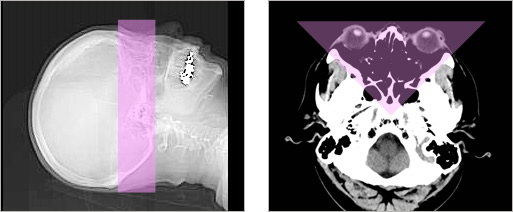

また、放射線の影響を受けやすい領域への被ばくを下げる機能(ODM)も搭載されています。 例えば、眼の水晶体へODM(ピンク色)を設定した場合には、画像クオリティーを下げることなく、最大で約30%の放射線量を自動で減らすことができます。